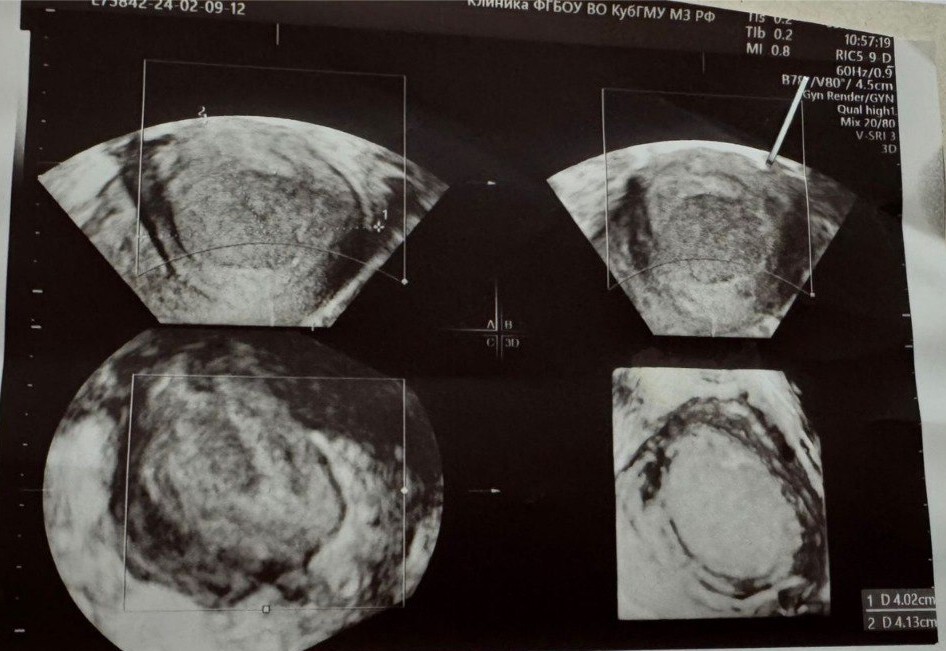

По данным УЗИ малого таза выявил кисту матки (жидкостное образование 40х50 мм. с толстыми стенками с характерным мелкодисперсным содержимым). Признаков кровотока в стенке образования не обнаружено. Так же отмечена диффузная неоднородность миометрия (признаки аденомиоза).